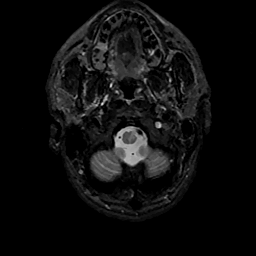

MR Study #11, May 5, 1991 -- Slice #3

[Home][Help][Clinical][Tour 1][Tour 2] Slice 3